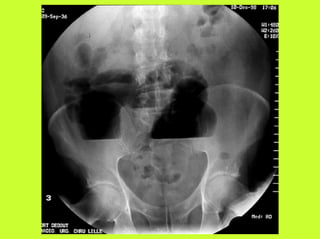

3) RADIO (PNO)

RADIOGRAPHIES

ABDOMEN SP -scanner

PNEUMOPERITOINE SUR SUJET DEBOUT

" Croissant gazeux sous diaphragmatique

" Disparition du niveau hydroaérique gastrique

PNEUMOPERITOINE SUR SUJET COUCHE

" Visibilité du ligament triangulaire du foie

" Visibilité anormale des parois intestinales

" Image aérique pré-hépatique

"Pneumatisation de MORRISSON

(cul de sac inter-hépato-rénal)

! ASP, pneumopéritoine important

RADIOGRAPHIES ABDOMEN SP -scanner PNEUMOPERITOINE SUR SUJET DEBOUT " Croissant gazeux sous diaphragmatique " Disparition du niveau hydroaérique gastrique PNEUMOPERITOINE SUR SUJET COUCHE " Visibilité du ligament triangulaire du foie " Visibilité anormale des parois intestinales " Image aérique pré-hépatique "Pneumatisation de MORRISSON (cul de sac inter-hépato-rénal) AUTRES EXAMENS "TOGD aux hydrosolubles? " Echo, scanner " Coelioscopie ? " Pas de lavement colique, pas de fibroscppie, pas de coloscopie, pas d’IRM